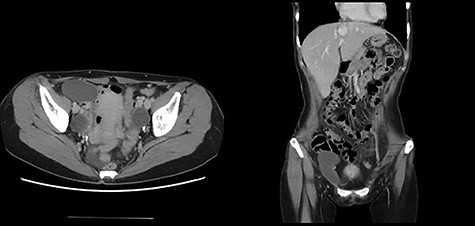

A 49-year-old woman presented with painless swelling in her right inguinal region. She had a history of caesarian section and no history of infantile inguinal hernia. Physical examination revealed a soft egg-shaped mass extending from the right inguinal region to the labia majora. The mass was seen as a protrusion when the patient was in the standing position, while it disappeared when the patient was in the lying position. Ultrasound revealed a well-defined hypo-echoic elongated mass that extended from the superficial inguinal canal, with no solid component (Fig. 1). Computed tomography (CT) showed that 55 × 34 × 95 mm oval fluid collection located at the right inguinal region near the cecum and retroperitoneum in the abdominal cavity (Fig. 2). Total colonoscopy found no mucosal abnormalities from the cecum to the rectum; however, a mass of tissue pushed the cecal wall from outside (Fig. 3). This hinted toward a large HCN, appendiceal tumor or retroperitoneal tumor; we decided to attempt a combined approach of conventional and laparoscopic methods for diagnosis and treatment of the swelling. We used three ports (12, 10 and 5 mm; Fig. 4) for our laparoscopic approach. We placed a 12 mm laparoscopic trocar into the umbilicus for CO2 insufflation of the pneumoperitoneum. Endoscopic intraperitoneal observation revealed that the mass was distant from the cecum and outside the peritoneum (Fig. 5). The tumor was large and was not completely observed using only an intra-abdominal approach. Therefore, we used a combined approach, which was the conventional method with a skin incision in the inguinal region in addition to the intra-abdominal method with laparoscopic approach. The tumor could be resected without any damage by observing from both directions (Fig. 6). We adopted the Direct Kugel Patch (ONFLEX®, C.R. Bard, Inc., USA) for the vulnerability of the posterior wall of the inguinal canal. Histopathological examination revealed that the mass contained single-layered mesothelial cells and no tumor or endometriosis. Based on imaging, histopathology and operative findings, we diagnosed her with an HCN. The patient recovered and did not have any postoperative complications, and she was discharged from hospital on postoperative day 6. She had no recurrence of hernia or hydrocele until 16 months postoperatively.

It is very difficult to diagnose the HCN preoperatively. In cases where the HCN communicates with the peritoneal space, it often mimics an inguinal hernia in women because of its changeable mass [7]. There are many differential diagnoses for masses of the inguinal region besides HCN. Enlarged lymph nodes and soft tissue tumors (lipomas, leiomyoma and endometriosis of the round ligament) may cause inguinal or femoral hernias. In rare cases, vascular abnormalities, ganglion cysts, appendiceal tumor or retroperitoneal tumor may form the inguinal mass [4]. It would be difficult to diagnose the HCN solely based on physical findings [8]. In the present case, the tissue mass was huge, and we could not definitively diagnose it as HCN. Contrast-enhanced CT revealed a large oval fluid collection located in the inguinal region next to the cecum and retroperitoneum; thus, it was difficult to determine the exact origin of the cells from which the tumor could be derived. Because the mass could be potentially associated with an adverse abdominal condition (e.g. appendiceal or retroperitoneal tumor), it was necessary to identify the origin of the mass by observing the abdominal cavity.